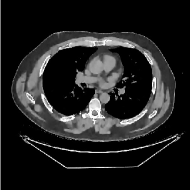

This section compares the reconstruction quality and runtime among the proposed MBIR method, PWLS-ST-, and other three MBIR methods, PWLS-EP, PWLS-DL, and PWLS-ST-. Table I shows that, for both 2D and 3D sparse-view CT reconstructions of the XCAT phantom, the proposed PWLS-ST- model outperforms PWLS-EP and PWLS-ST- in terms of RMSE. In addition, PWLS-ST- using a square transform (of size ) achieves lower RMSE than PWLS-DL using an overcomplete dictionary (of size ) for 2D sparse-view reconstructions. Fig. 3(a) and Fig. 4 show the reconstructed images for 2D and 3D phantom experiments, with different reconstruction models and different number of views. (See the corresponding error maps in the supplement.) The proposed PWLS-ST- consistently gives more accurate image reconstructions compared to other MBIR methods. Specifically, PWLS-ST- has smaller errors in the heart region (see zoom-ins in Fig. 3(a)) of 2D reconstructions than PWLS-DL and PWLS-ST-. In addition, compared to PWLS-ST-, PWLS-DL and PWLS-ST- have some ringing artifacts around the edges with high transition, e.g., edges between air and soft tissues. (See a comparison of profiles of PWLS-ST- and PWLS-ST- in the supplement.) In particular, PWLS-ST- and PWLS-DL give more visible ringing artifacts for 2D reconstruction from fewer views, and PWLS-ST- has these ringing artifacts for 3D reconstructions regardless of the number of views (see zoom-ins in Fig. 4). Table II reports runtimes of different MBIR methods in reconstructing the -views XCAT phantom scan. (FBPConvNet is a non-MBIR method and its runtime for processing a image is approximately one second with a TITAN Xp GPU.) While providing better reconstruction quality, the proposed Algorithm 1 of PWLS-ST- has shorter runtime compared to the algorithms of PWLS-DL and PWLS-ST- in Section III-A. Similar to the PWLS-EP algorithm, the reconstruction time of the PWLS-DL, PWLS-ST-, and PWLS-ST- algorithms can be further reduced by using ordered subsets [51].

Fig. 3(b) shows that when tested on the clinical scan data, the proposed PWLS-ST- method improves reconstruction quality in terms of noise and artifacts removal (e.g., see zoom-ins for soft-issue regions), and edge preservation (e.g., see zoom-ins for bone regions), compared to PWLS-EP and PWLS-ST-. Compared to PWLS-DL, PWLS-ST- achieves comparable image quality, but requires less computational complexity.

![]() |

| (a) 2D fan-beam CT experiments |

| (b) 3D axial cone-beam CT experiments |